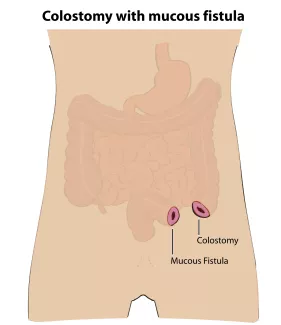

If the rectum ends high in the pelvis and is too far from the skin, surgical repair will be done in stages. First a stoma, or connection of the colon to the skin on the abdominal wall will be created.

An opening, called the colostomy, will allow stool to pass into a bag. The second opening is called the mucous fistula and allows the closed end of the rectum to drain fluid or mucous as needed. After this operation, the baby can go home to recover and grow.